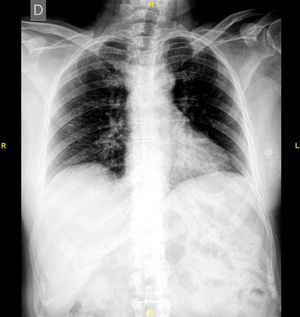

En el estudio de extensión de la enfermedad solicitado, se evidenció imagen gammagráfica de lesión blástica, difusa, en el manubrio esternal, sospechosa de enfermedad de Paget o de lesión metastásica (fig. 1). Se completó el estudio con radiografías de tórax, columna lumbosacra y pelvis (figs. 2 y 3), en las que solo se evidenció aumento de densidad interapofisaria de L4 y L5. Posteriormente, se solicitó TC torácico, según recomendaciones de Medicina Nuclear, que informó de esclerosis en el manubrio esternal, sugerente de metástasis (fig. 4).